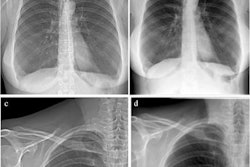

Figure 2: (A, C) Conventional attenuation-based chest x-rays and (B, D) dark-field chest x-rays in an 83-year-old man diagnosed with combined pulmonary fibrosis and emphysema (upper row) and a healthy 33-year-old man (lower row). Image courtesy of Radiology: Cardiothoracic Imaging.The patient (Fig 2: A, B) demonstrated substantially decreased dark-field signal in the upper lungs (left more than right), where emphysema is most severe, and inhomogeneous but decreased lower lung signal (due to presence of fibrosis) when compared with a healthy subject (Fig 2: C, D). The stronger manifestation of fibrosis in the right lower lobe compared with the left lower lobe, as was seen on CT images, corresponded well to the asymmetric reduction of dark-field signal in the lower fields with a right-sided predominance (Fig 2B), the authors wrote.